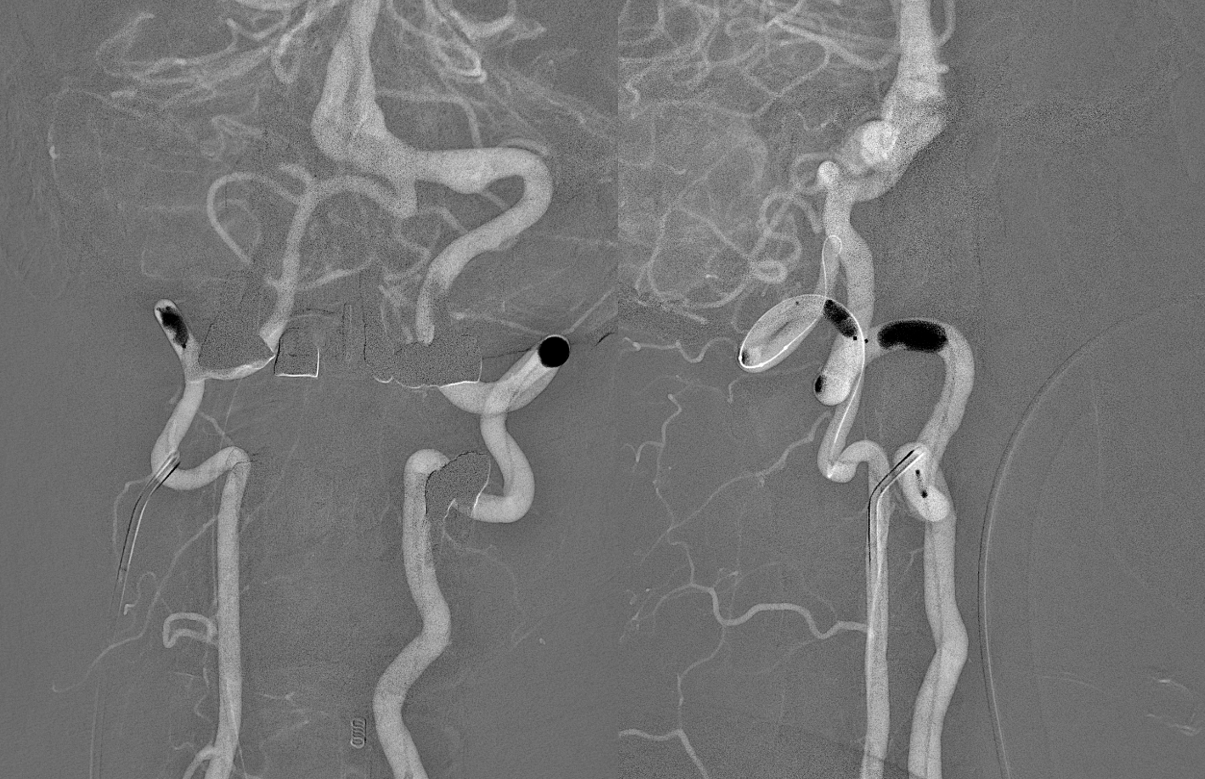

Giant basilar presents with perforator occlusion:

Angio — left ICA. It takes about 2 seconds to fill this aneurysm completely from start of injection (not shown)

Angio dominant left vert frontal. This injection does not completely fill the aneurysm, and does not visualize the right vert. therefore, these settings would not be good for a “spin” — no 3D or DYNA or Vaso or whatever. The injection needs to be stronger or should be done bilaterally.

Lateral view

Hypoplastic (or smaller) right vert injection. Must be done to understand PICA and perforators between PICA and the VB junction. You can see there are many even on 2D – -because the AICA is dominant and there is a small PICA, so expect intradural perforators.

Now, notice that there is a PCOM on left ICA injection. Thats unusual for this aneurysm. There is also a small one on the right. So, we will do DYNA and then Balloon Test Occlusion of both verts.